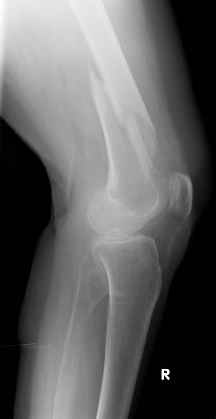

Видно спиральный перелом дистального метадиафиза бедра. У нас бы сделали антеградный закрытый интрамедуллярный остеосинтез.

Для фиксации такого перелома можно применить чуть не все методы - и клинковую пластину, и мыщелковую (и обычную, и Locked), и LISS, и анте-, и ретроградный гвоздь, и аппарат... Интересно, какими факторами надо руководствоваться при выборе, если доступно все перечисленное?

>Попробуяю угадать - ретроградный гвоздь?

Вы угадали.